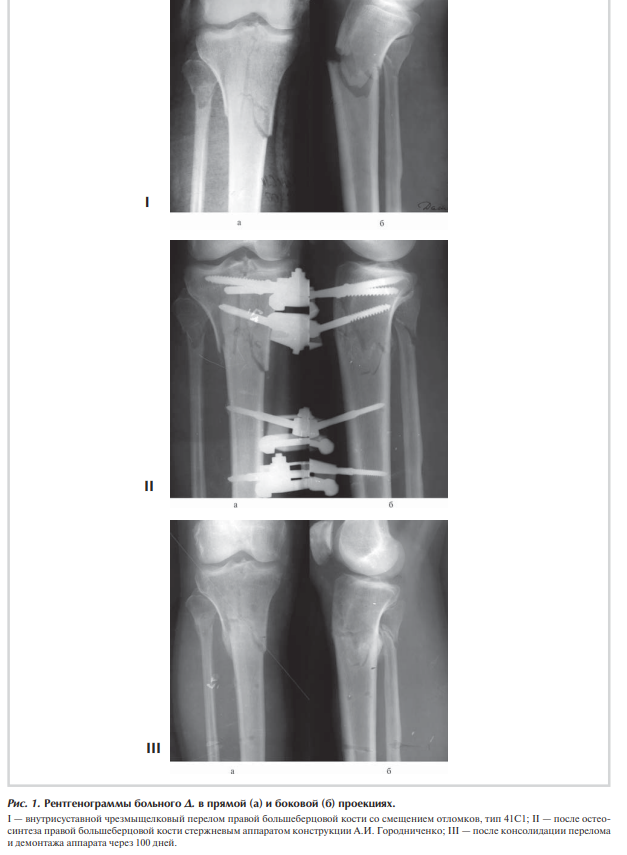

При осмотре отмечаются отек правого коленного сустава и верхней трети голени, болезненность при пальпации и положительный симптом баллотации правого надколенника. После клинико-рентгенологического обследования установлен диагноз: закрытый внутрисуставной чрезмежмыщелковый перелом правой большеберцовой кости со смещением отломков, тип 41С1 (рис. 1, I).

Сосудистых и неврологических расстройств в дистальных отделах правой нижней конечности не выявлено. При поступлении произведена анестезия места перелома, при пункции правого коленного сустава получено 60 мл крови с примесью жира, выполнена внешняя иммобилизация конечности гипсовой лонгетной повязкой. На следующий день под наркозом произведена операция: закрытая репозиция и чрескостный остеосинтез правой большеберцовой кости стержневым аппаратом конструкции А.И. Городниченко. Через разрезы кожи и мягких тканей по передневнутренней поверхности правой голени длиной до 8 мм введено три спонгиозных стержня в мыщелки большеберцовой кости и три кортикальных стержня в диафизарную часть. После фиксации проксимальных стержней в аппарате под контролем электроннооптического преобразователя произведена закрытая репозиция с помощью съемных рукояток с последующей стабилизацией дистальных стержней (рис. 1, II). Кожа вокруг стержней ушита одиночными швами.

Послеоперационное течение без осложнений, проводили регулярные перевязки с обработкой кожи вокруг стержней растворами антисептиков и сменой асептических повязок. Швы вокруг стержней сняты через 12 дней после операции, и пациент выписан на амбулаторное лечение с рекомендациями по дальнейшему восстановительному лечению. После консолидации перелома через 100 дней произведен демонтаж аппарата (рис. 1, III).

Движения в правом коленном суставе перед демонтажем аппарата от 0 до 140° (рис. 2).